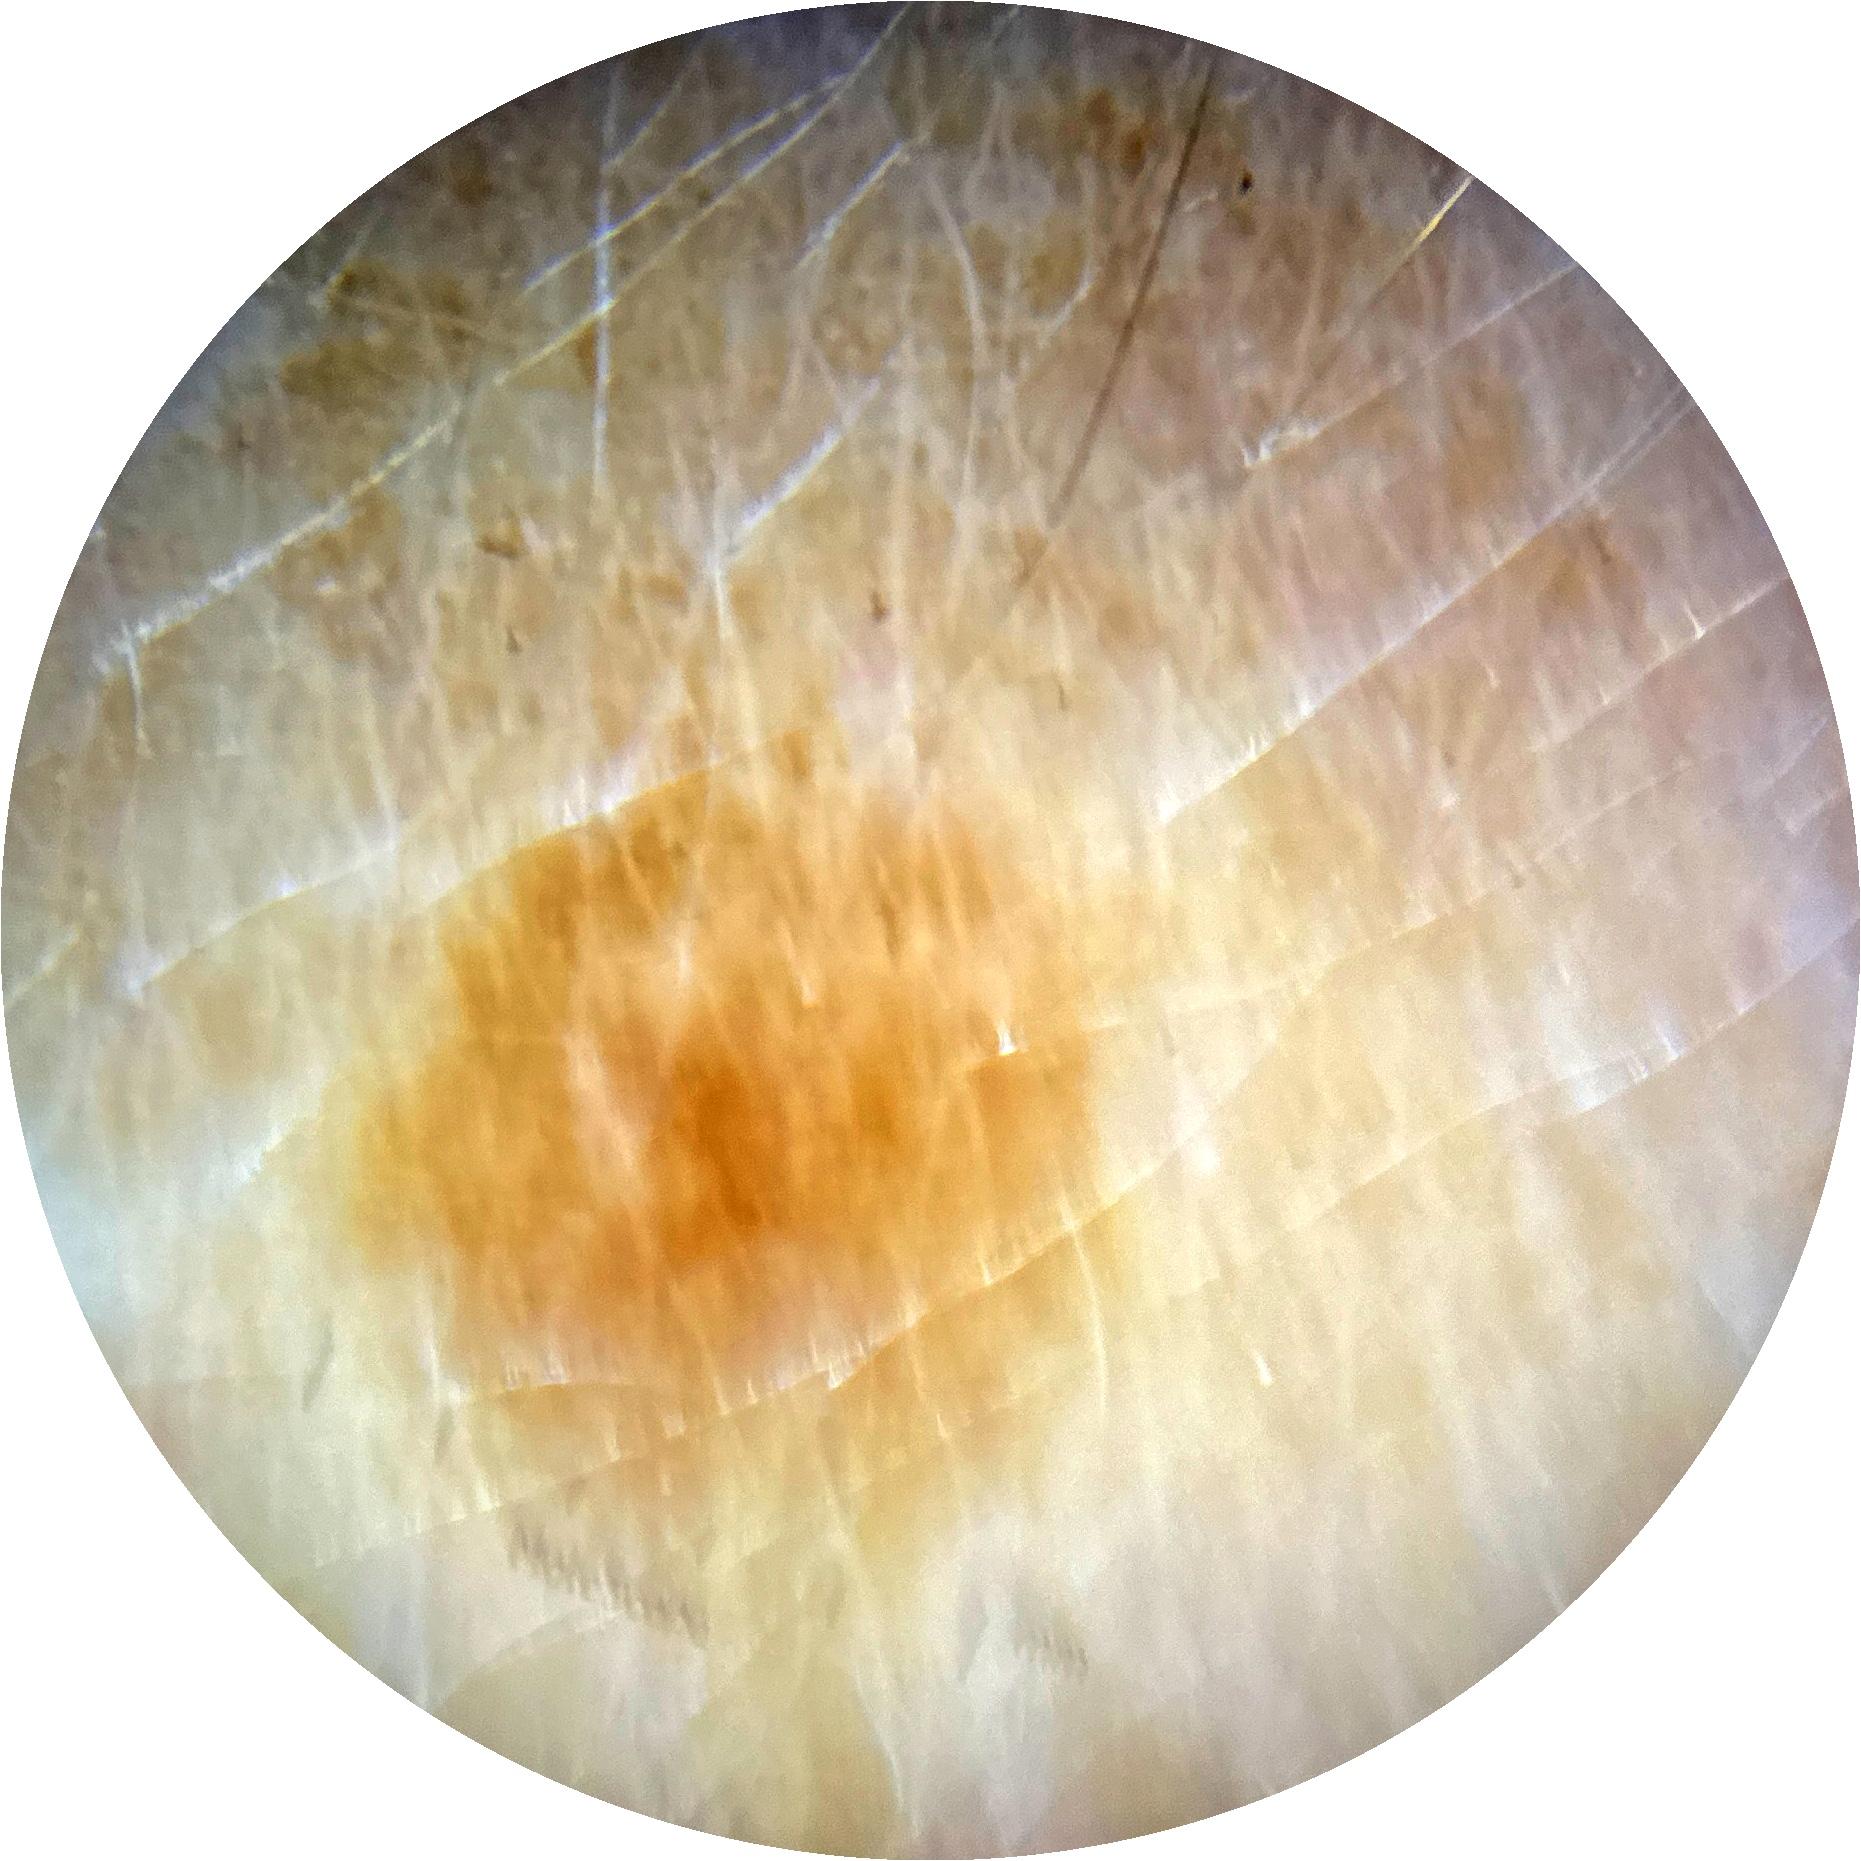

ISIC_5925053

1887 x 1887

acquisition_day 325

age_approx 60

anatom_site_1 Upper extremity

diagnosis_1 Benign

diagnosis_confirm_type single image expert consensus

fitzpatrick_skin_type I

image_type dermoscopic

personal_hx_mm True

sex female